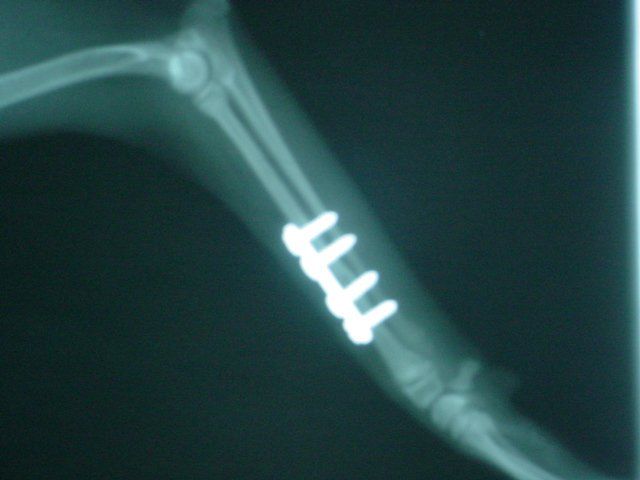

Dogs and cats commonly experience fractures secondary to trauma. The most common cause of the trauma is being hit by a car. Other trauma such as falls from furniture, jumping on unstable surfaces, leaping from a person's arms, etc. can also result in fractures. Below are some x-rays of some of the fractures we have seen at All Pets and their surgical correction using pins, plates, screws, and/or wires.